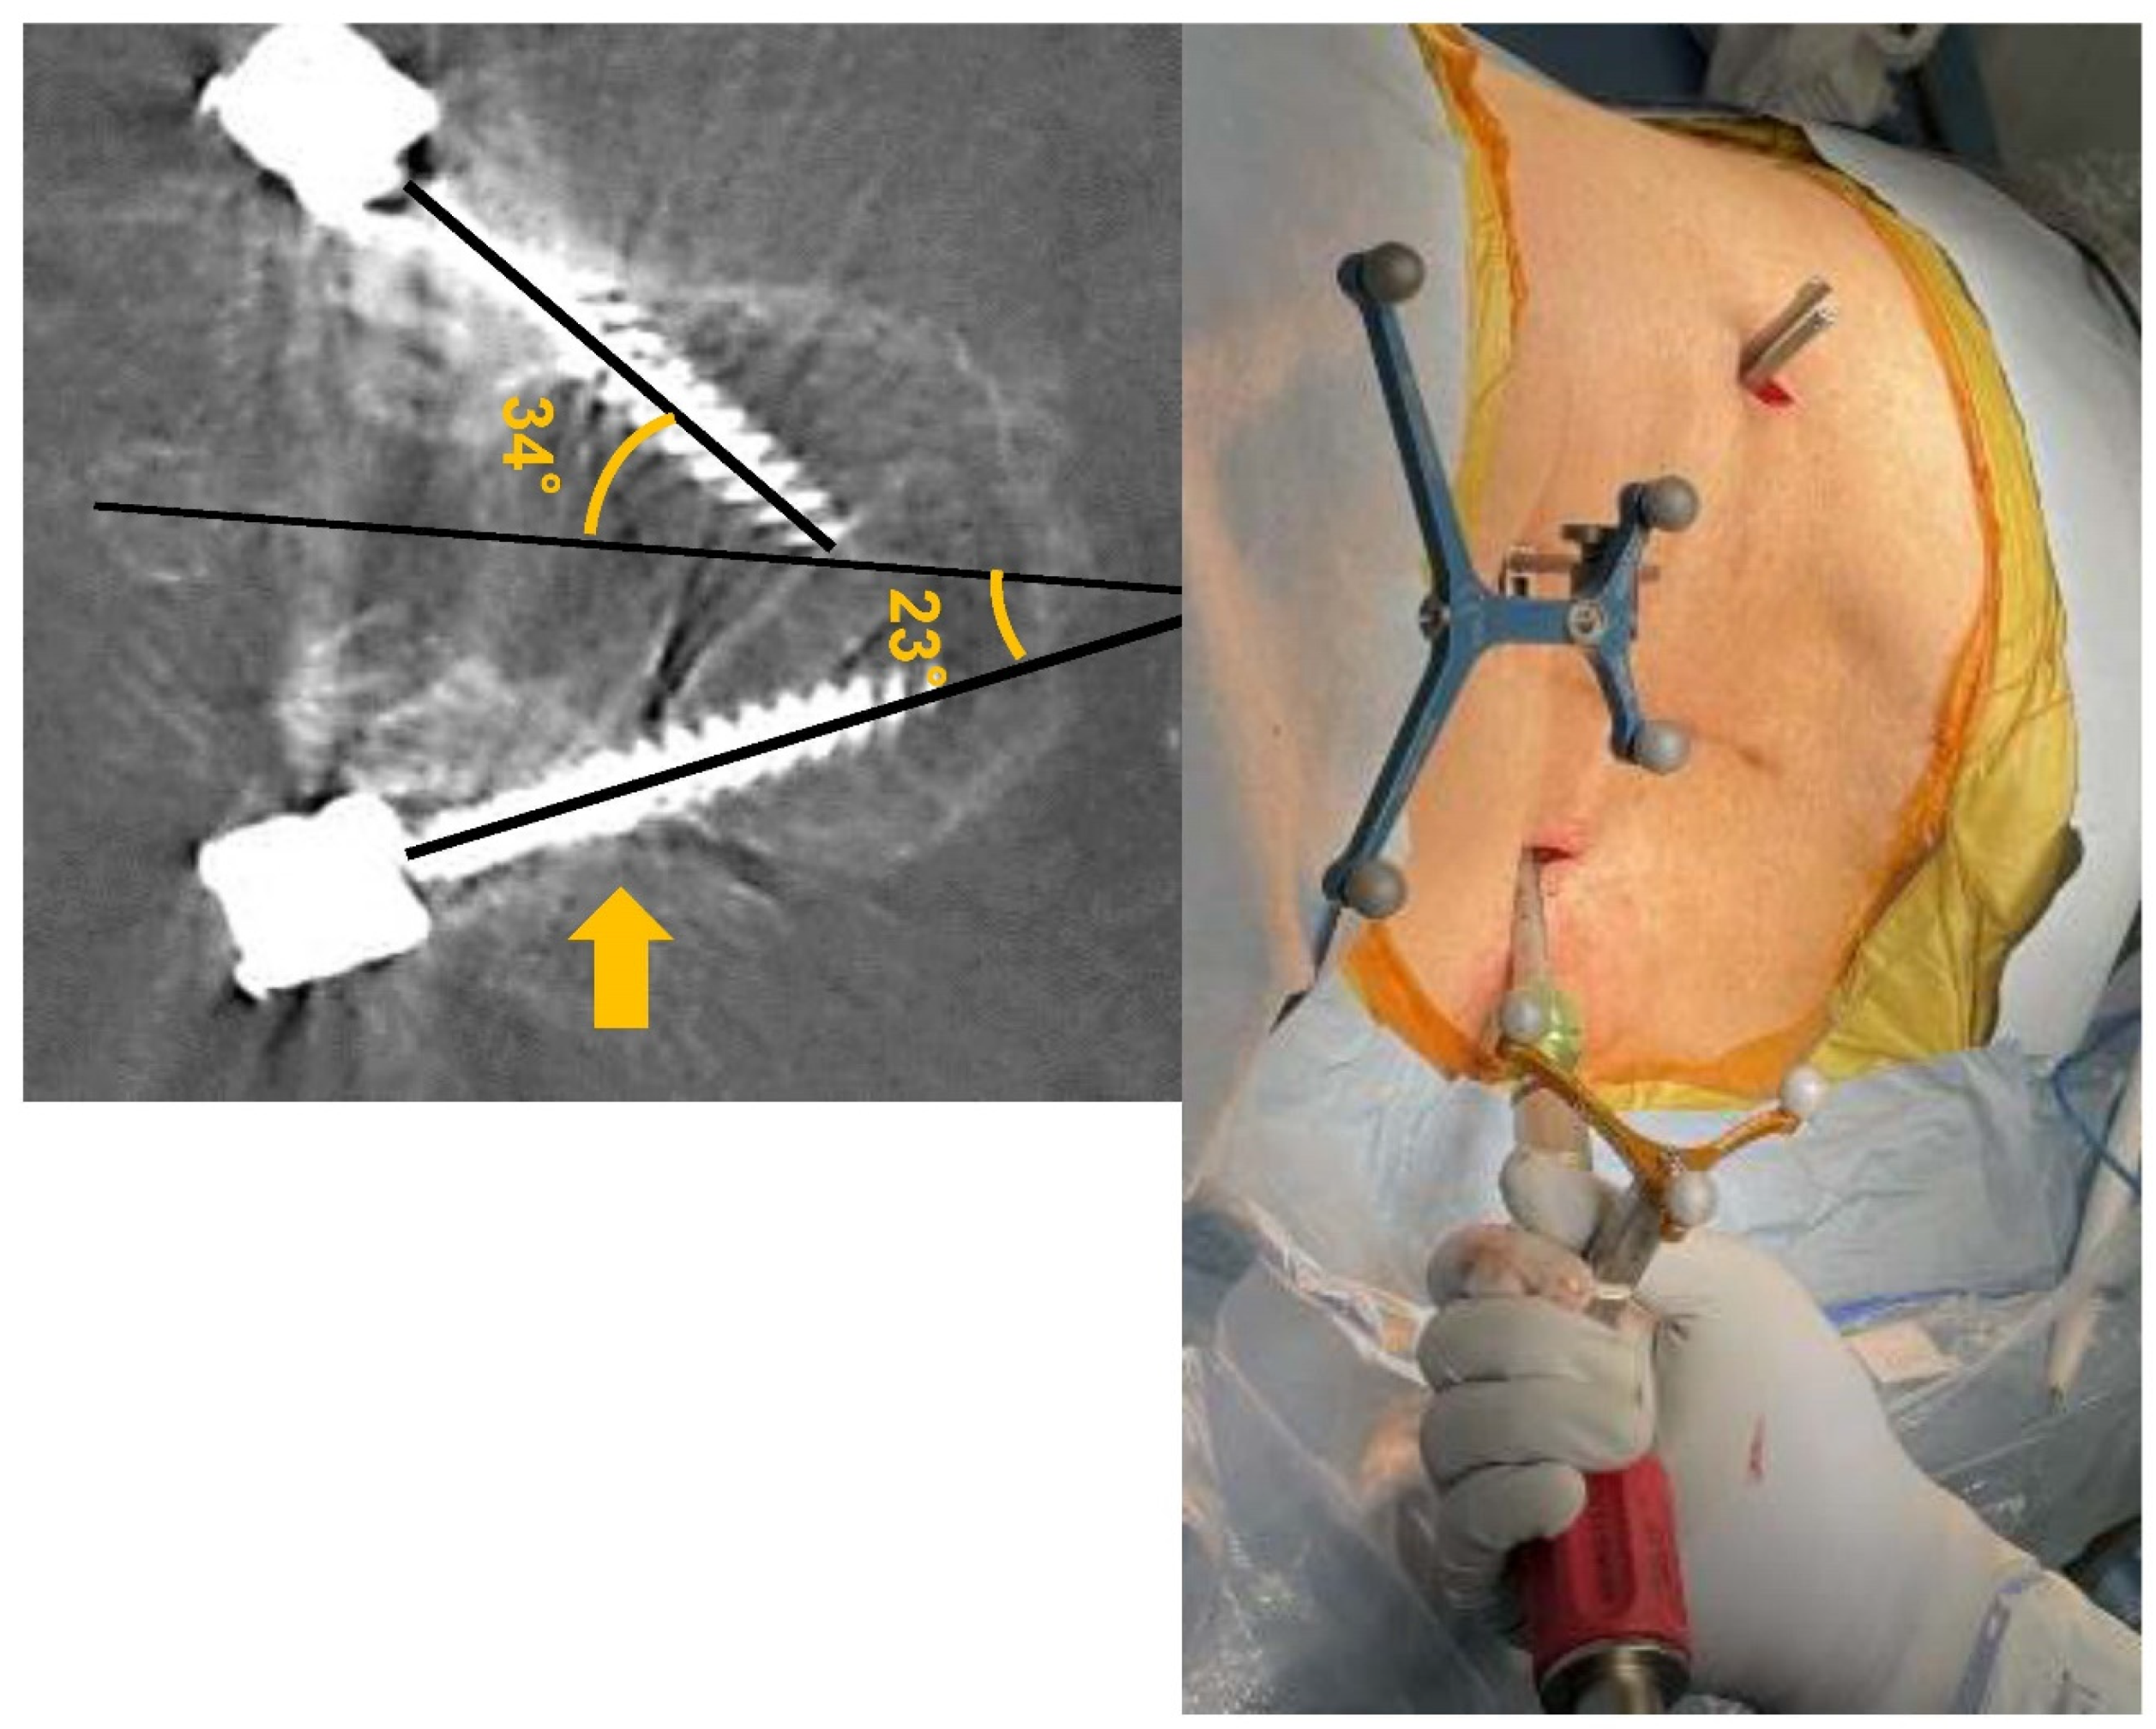

The radiographic outcomes (screw trajectory angles and accuracy of PPS) of patients in the three groups are shown in Table 2. There was no significant difference in the screw trajectory between groups on the upside (34.8 ± 7.1° vs. 34.2 ± 7.6° vs. 34.1 ± 5.6°, respectively; p = 0.9). In contrast, the screw trajectory on the downside was significantly smaller in patients in the LD group than in patients in the DP and O groups (30.1 ± 6.1° vs. 33.9 ± 6.6° vs. 33.6 ± 6.2°, respectively; p < 0.05). Overall, the frequency of no misplaced screws (Grade 1) in patients in the LD group was significantly lower than that in patients in the DP and O groups (125/148 (84.4%) vs. 181/198 (91.4%) vs. 173/188 (92%), respectively; p < 0.05). For the upside screws, there was no significant difference in the accuracy between the groups. In contrast, the frequency of no misplaced downside screws was significantly lower in patients in the LD group than in patients in the DP and O groups (58/74 (78.4%) vs. 90/94 (91.0%) vs. 87/94 (92.6%), respectively; p < 0.05). Grade 3 misplaced screws were only seen upside in patients in the LD group (4/94, 4.3%). There were no occurrences of neurovascular injury due to screw placement in either group, and no revision surgery was needed in these groups.

Knowledge of the effectiveness and safety of LLIF and PPS using intraoperative CT image-guidance navigation has been reported in recent years and is rapidly spreading [9,18,19]. Nevertheless, concerns about increasing the exposure of patients to radiation by using CT image-guided navigation instead of traditional guidance with fluoroscopy (C-arm) have been reported [20]. Conventional LIF-PPS fixation with CT image-guided navigation with patients in two (dual) positions requires at least two scans. In the present study, there were no patients in the single-position group who required reimaging with an O-arm, and all patients underwent surgery after a single scan. This result indicated that single-position surgery also had advantages in terms of reducing patient exposure. Consistent with previous reports, a single-position procedure reduces surgical time by approximately 60 min compared with the conventional dual-position procedure. Additionally, eliminating the need for intraoperative repositioning to the prone position is associated with reduced medical costs and complications such as postoperative vision loss and cardiovascular complications, including hypovolemia and cardiac arrest [21,22]. Because of these advantages, the single-position procedure is currently attracting attention as a useful method. However, concerns remain about the pitfalls and the surgeon’s learning curve for PPS placement in the lateral position [23]. Recent reports have indicated that for PPS downside placement in the lateral position, attention was needed to avoid a lateral breach, which was considered to be related to the inability of the surgeon to place the screws medially due to obstruction from the operative bed [24,25]. Our data also showed a significantly lower accuracy for PPS downside placement in the LD group (Figure 3). Another concern for lateral position surgery was increased blood loss, because gravity makes it easier for blood to drip [9]. An advantage of intraoperative CT navigation is that there is no need to adjust the fluoroscopic image after bed rotation. Recently, single-position surgery for lumbar circumferential fusion with patients in various positions has been suggested, such as prone-position LLIF, lateral-position ALIF, and their combination [26]. We considered that bed rotation could be useful to achieve a more advantageous surgical position for each procedure that PPS demonstrated in the oblique position and LIF demonstrated in the lateral position, and the present study indicated an oblique position during PPS insertion that might make single-position surgery more useful to improve the accuracy of the PPS downside placement and to reduce blood loss. Numerous studies have compared single-position surgery and conventional surgery with repositioning for LIF-PPS for lumbar fusion. But among them, to our knowledge, the present study is the first to compare a single lateral position and oblique position during PPS in LIF-PPS for lumbar fusion. Another concern with this procedure was the accuracy of navigation in single lateral or oblique position. Few studies have examined the accuracy and reality of intraoperative CT navigation in lateral approaches to the spine [18]. In our previous study, we reported that most navigation errors in spinal surgery using intraoperative O-arm navigation occur when the position of the reference frame shifts during the surgical procedure near the reference frame [27]. Based on these experiences, we devised a procedure to fix the reference frame strongly to the spinous processes 1–2 vertebrae cephalad of the intervertebral body to be fixed and to perform PPS prior to LIF to avoid the navigation errors caused by intervertebral expansion and/or correction associated with the cage insertion of the LIF. As a result of those efforts, there were no cases in the present study in which the cage or screw insertion position was misaligned due to navigation errors, and there were no cases in which O-arm reimaging was necessary.

Figure 3.

Axial CT and photographs of a representative case of the PPS downside placement in the lateral position; attention was needed to avoid a lateral breach. PPS, percutaneous pedicle screw. Yellow arrows indicate deviation outside of screw.